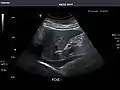

Renal ultrasonography

Ultrasound scan of a kidney (right side)

Ultrasonography of the kidneys is essential in the diagnosis and management of kidney-related diseases. The kidneys are easily examined, and most pathological changes in the kidneys are distinguishable with ultrasound.[7]